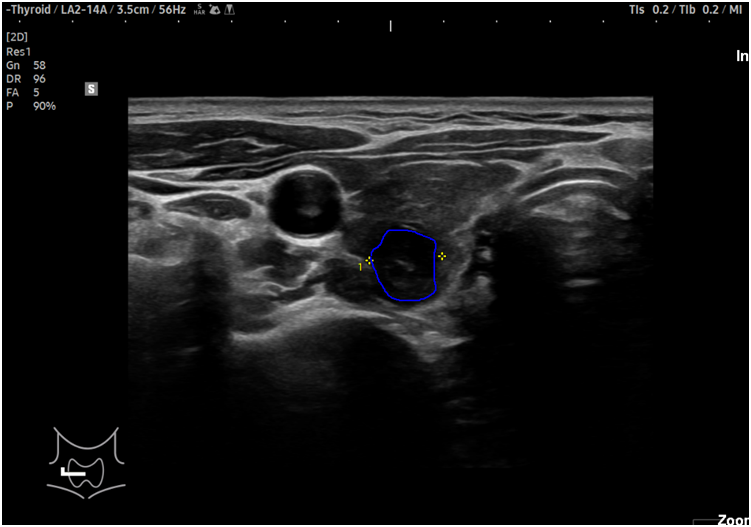

갑상선 세침 흡인 검사

갑산선 세침 흡인 검사는 초음파 진단 시 결절이 있는 경우 암 여부를 진단하기 위한 검사입니다.

주사기로 결절 부위의 조직을 얻는 검사로 매우 가는 주사바늘을 이용하여 통증이나 부작용이 없고 간단하고 안전한 장점이 있습니다.